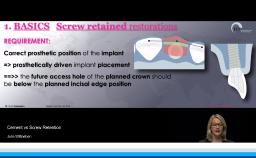

This lecture also gives an overview of implant-assisted partial RDPs, addressing support, retention, and esthetics in combination with tooth replacement, ridge preservation, and full-arch conversion. Unsplinted and splinted implant prosthodontic options for retention are presented. Finally, emphasis is placed on the importance of using implants as part of longer-term planning for the patient’s dentition.